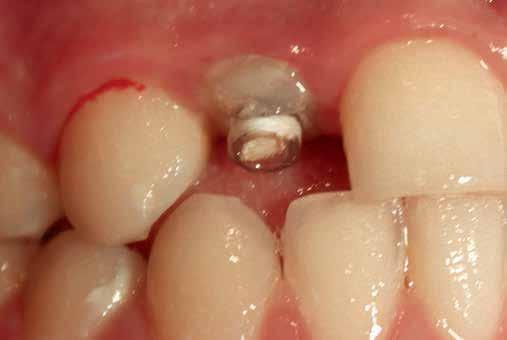

The prosthetic procedures for definitive restorations were performed 3 months after implant placement. The healing abutment was removed (Fig 10) scan body was placed in position and a digital implant-level impression was made using an intraoral scanner (Medit I 700 3D scanners) (16) (Fig 11,12)